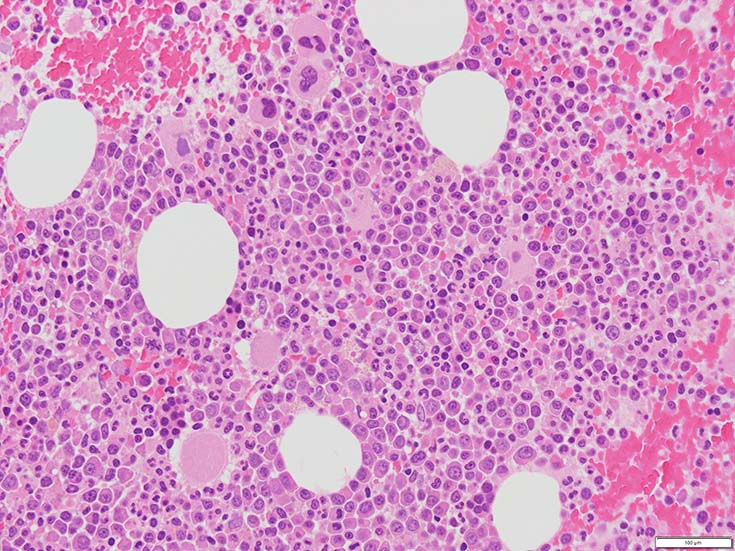

初診時の骨髄組織所見

70-80%のhypercellular marrow. 3系統造血細胞が認められる. Naphtol-ASD-CAE染色で赤色にそまる顆粒球系細胞増生が顕著な骨髄組織.

promyelocytesなど幼若顆粒球系細胞の集簇がみられるが, 分葉好中球他, 成熟顆粒球(Naphtol-ASD-CAE染色は薄く染まる傾向あり)も多く認められacute leukaemiaの所見ではない.

単球(Naphtol-ASD-CAE染色陰性)が密に増殖する所見は骨髄組織には認められない(*1)